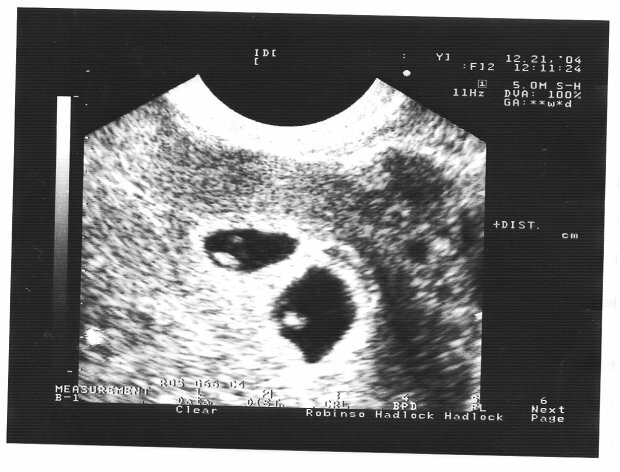

Bliźniaczki “pokłócili się” w łonie matki:

Nagranie z badania USG zostało opublikowane przez Chińczyka na imie Tao z miasta Yinchuan – w mediach społecznościowych ten filmik polubiło aż dwa i pół miliona osób. Na nagraniu widać, że bliźniaczki niczym przepychają się swoimi małymi pięściami i „bija się”. Przyszły tata powiedział, że to widowisko przypomniało mu mecz bokserski. O tym pisze Daily Mail.

Tak naprawdę przyczyna takiego zachowania dzieciaków było to, że oni znajdują się w jednym worku owodniowym, podczas gdy zwykle każdy z bliźniaków ma własny worek. Dzieje się tak w około 1% ciąż bliźniaczych.